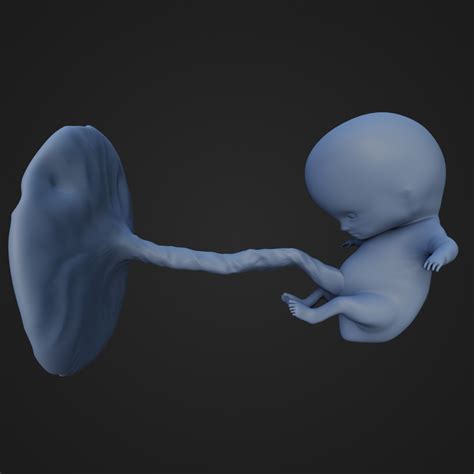

9 Week Baby

Welcoming a new baby into the world is an exciting and transformative experience. As parents, understanding the developmental milestones of a 9 week baby can help you provide the best care and support for your little one. This guide will walk you through the key aspects of a 9 week baby's growth, including physical development, cognitive skills, and emotional needs.